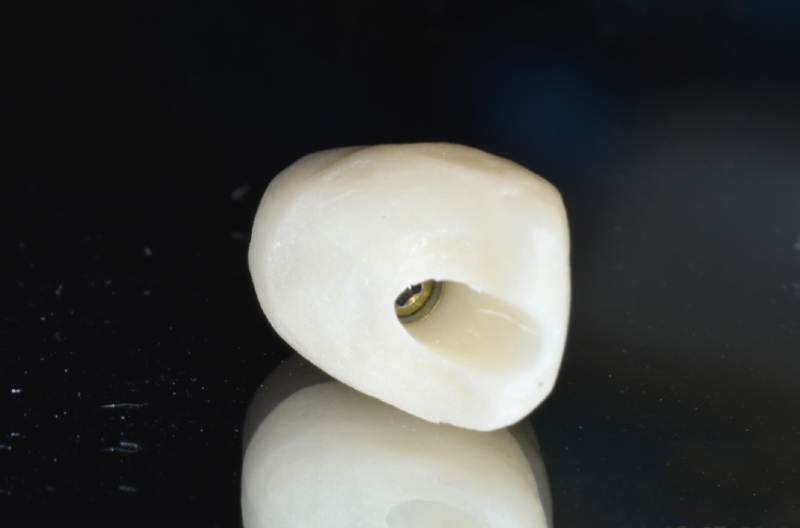

Finished temporary screw-retained crowns

View of the screw channel